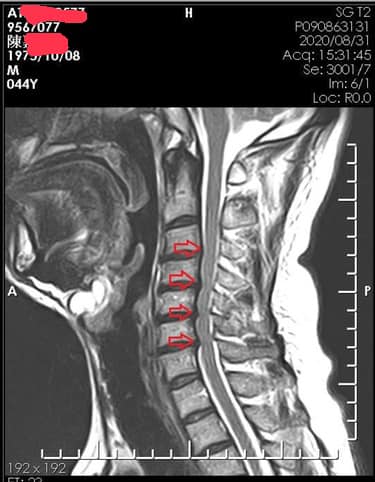

Cervical Spine Treatment Cases 頸椎治療案例 頸椎壓迫竟導致自律神經失調?耳鳴、心悸、暴瘦全因筋膜失衡! 2021.02.18 頸椎壓迫神經根導致工作受限?非手術微創療法改善關鍵公開 2021.02.17 頸椎脊髓壓迫五大症狀公開!你也有雙腳沉重、手腳麻電感嗎? 2021.01.15 長期頭痛吃藥沒效?小心你可能是「頸源性頭痛」患者 2021.01.07 #感謝新北市蘆洲區楊先生熱情見證 #頸椎病變引起肩膀痠痛無法睡眠 #曾經大痛到想立刻... 2020.12.31 #感謝新北三重劉小姐熱情見證 #神經根型頸椎病經典案例 #曾經手麻痛到無法騎摩托車 #... 2020.12.25 #遠從台東縣的熱情見證 #五個多小時的車程三百多公里很辛苦 #疼痛超過兩年打過頸椎三... 2020.12.24 #頸椎酸痛到無法睡覺是怎們回事 #醫學中心證實頸椎間盤突出 #神外醫師建議開刀但患者... 2020.12.19 #頸椎曲線弧度非常重要 #頸椎嚴重壓迫有可能逆轉嗎 #肩膀疼痛到不行合併走路都無力 #... 2020.12.09 頸椎退化壓迫神經根怎麼辦?大直林小姐四週見效的中醫微創療法 2020.12.08 #特殊案例長年過敏性鼻炎 #起因居然是頸椎交感神經筋膜壓迫 #打開椎動脈循環🔄找到解... 2020.12.05 #恭喜新店陳小姐頸椎療程畢業 #神經根型卡壓醫案 #頸椎整合中醫微創療法逆轉勝 #告別... 2020.11.24 #特殊案例頸椎手術後又再度突出案例 #感謝台中劉大哥熱情見證 #親自手捏醫師娃娃公仔... 2020.11.18 #頸椎病居然會導致手快速萎縮 #脊髓型頸椎病案例 #感謝高雄王大哥熱情見證 #頸椎整合... 2020.11.13 #神經根型頸椎病讓人痛到無法入眠 #感謝新店陳小姐熱情見證 #患者的疼痛日誌讓人感動 ... 2020.11.11 ← 上一頁 3 4 5 6 7 下一頁 →